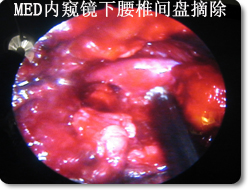

后路内窥镜下(METRx)腰椎管减压,椎间融合,经皮椎弓根螺钉(Sextant)复位内固定术

采用国际领先微创手术技术--后路内窥镜(METRx)行腰椎间盘摘除,椎管减压,并采用经皮椎弓根螺钉系统(Sextant)行复位和内固定。治疗腰椎间盘突出,椎管狭窄以及腰椎不稳等疾病。 优点:本手术采用Sextant系统通过小的皮肤切口直接放置腰椎椎弓根螺钉系统,经皮复位内固定,同时结合腰椎间盘镜(METRx)通过一个小切口(1.8cm)完成腰椎管减压,椎间植骨和融合器植入,本手术方式将Sextant技术与METRx技术相结合,以达到微创腰椎管减压、复位、融合和内固定。